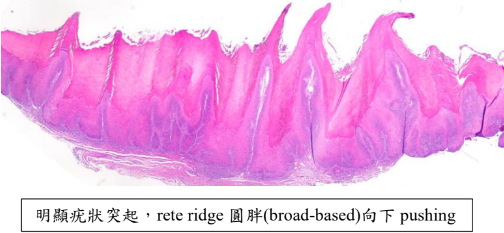

Verrucous Carcinoma(VC)

- Ackerman’s tumor

- 分化良好,不會鑽,用推的(Pushing) → 侵犯稍差

- HPV 低相關

- 四周可能有 SCC(20%)